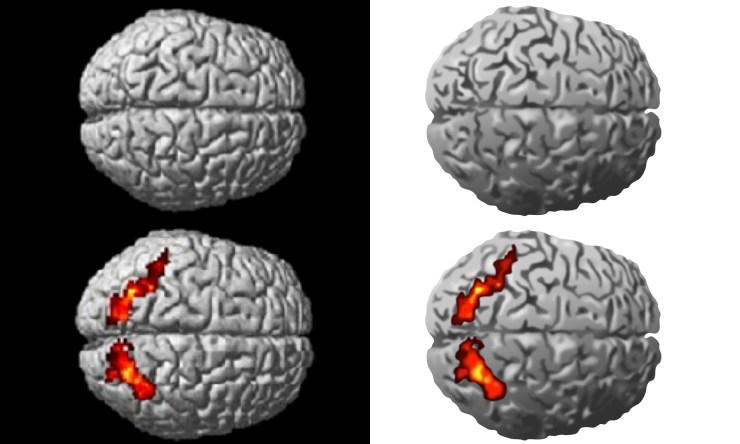

However, the illustration of an MRI scan showing the 3D brain is easier to draw and the results are show below, to the right of the original image. More detail could of course be added, but the illustration is already reasonably convincing. Also, any highlighted areas can easily be added in separate layers in Adobe Illustrator, to allow them to be switched on and off, as required.